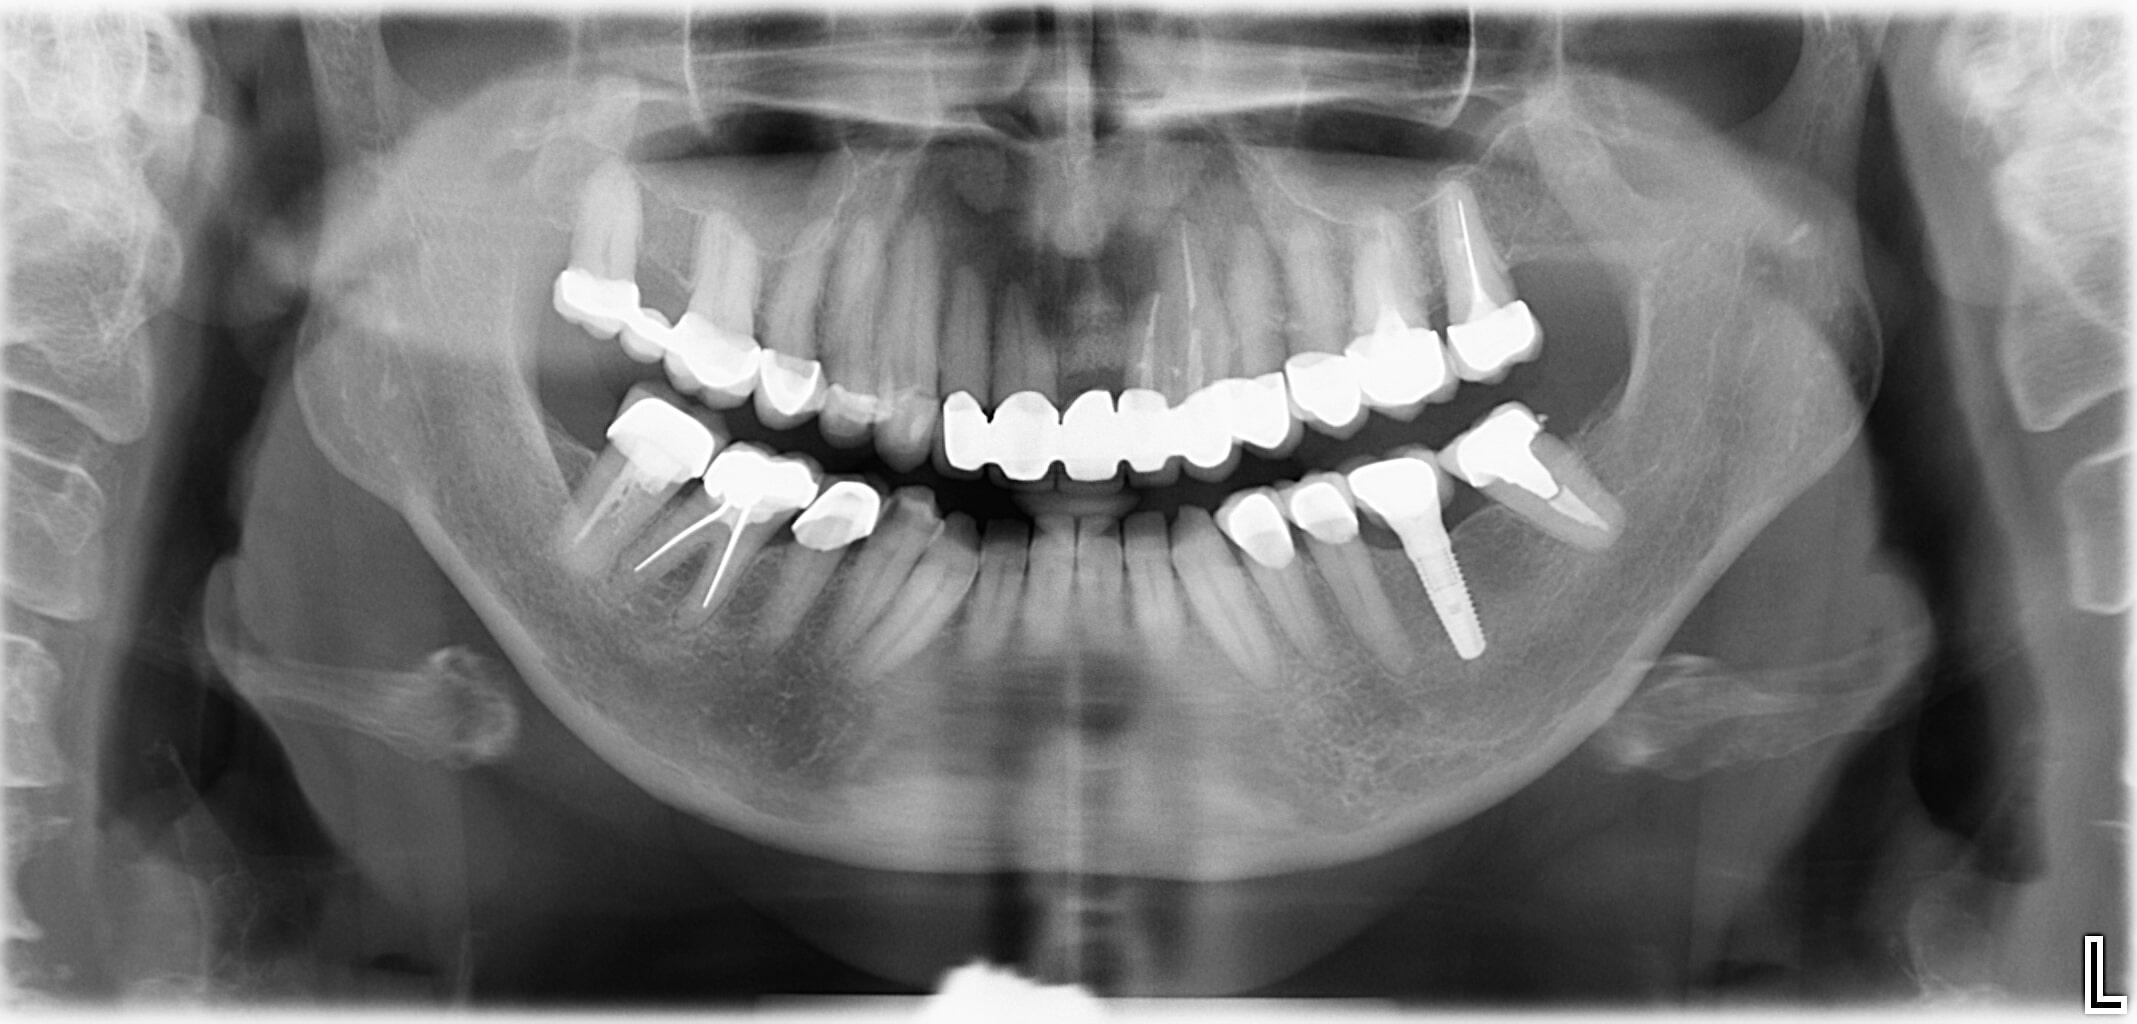

Und Sie denken dabei an eine nachhaltige Lösung mit einem Implantat? Dann machen Sie den ersten Schritt und vereinbaren Sie einen Beratungstermin in unserer Zahnarztpraxis Dr. Kaiser in Draßburg im Burgenland. Zahnimplantate ermöglichen einen dauerhaften Zahnersatz, der noch dazu sehr natürlich aussieht. Wir beraten Sie gerne und sorgen dafür, dass Sie Ihre schönen Zähne bei jedem Bissen und jedem Lächeln voll und ganz genießen können.

Unsere Zähne übernehmen nicht nur die Nahrungszerkleinerung, sie sind auch ausschlaggebend für unsere Aussprache und prägen vor allem unser Aussehen. Wer einen Zahn verliert, sei es durch einen Unfall oder als Folge einer Erkrankung, wünscht sich einen schönen und haltbaren Zahnersatz. Mit Zahnimplantaten können wir diese Wünsche vollends erfüllen.